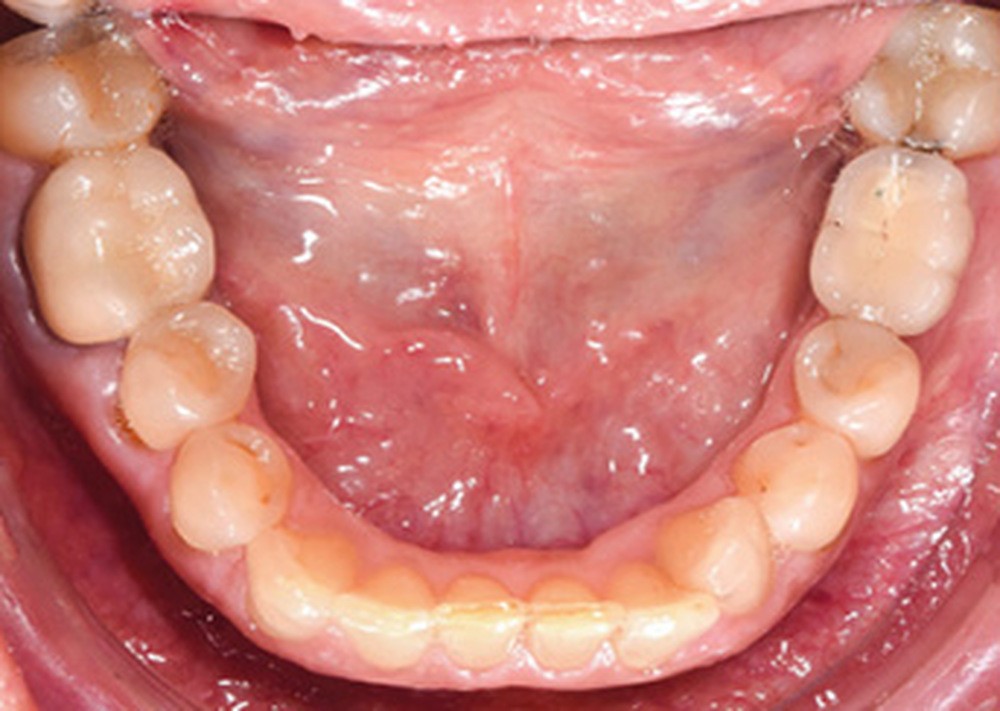

Discussion (fig. 5 à 8)

Le traitement a duré vingt-quatre mois. Les documents de fin de traitement nous montrent un sourire plus harmonieux et des rapports labiaux améliorés. De profil, la patiente a un meilleur soutien des lèvres. De plus, un léger repositionnement sagittal mandibulaire a été obtenu.

Sur la téléradiographie de profil, on note une normalisation des rapports incisifs avec un torque radiculo-palatin de l’incisive maxillaire et une vestibulo-version de l’incisive mandibulaire. La diminution de l’angle interincisif a été recherchée afin de garantir la stabilité du traitement. La superposition générale structurale révèle une rotation totale horaire qui confirme une amélioration du sens vertical.

La correction de la classe II molaire et canine a été réalisée tout en maintenant les médianes incisives centrées malgré l’implant en 36.

Il subsiste néanmoins un tip back de la 23 dû à l’effet parasite de la distalisation maxillaire.